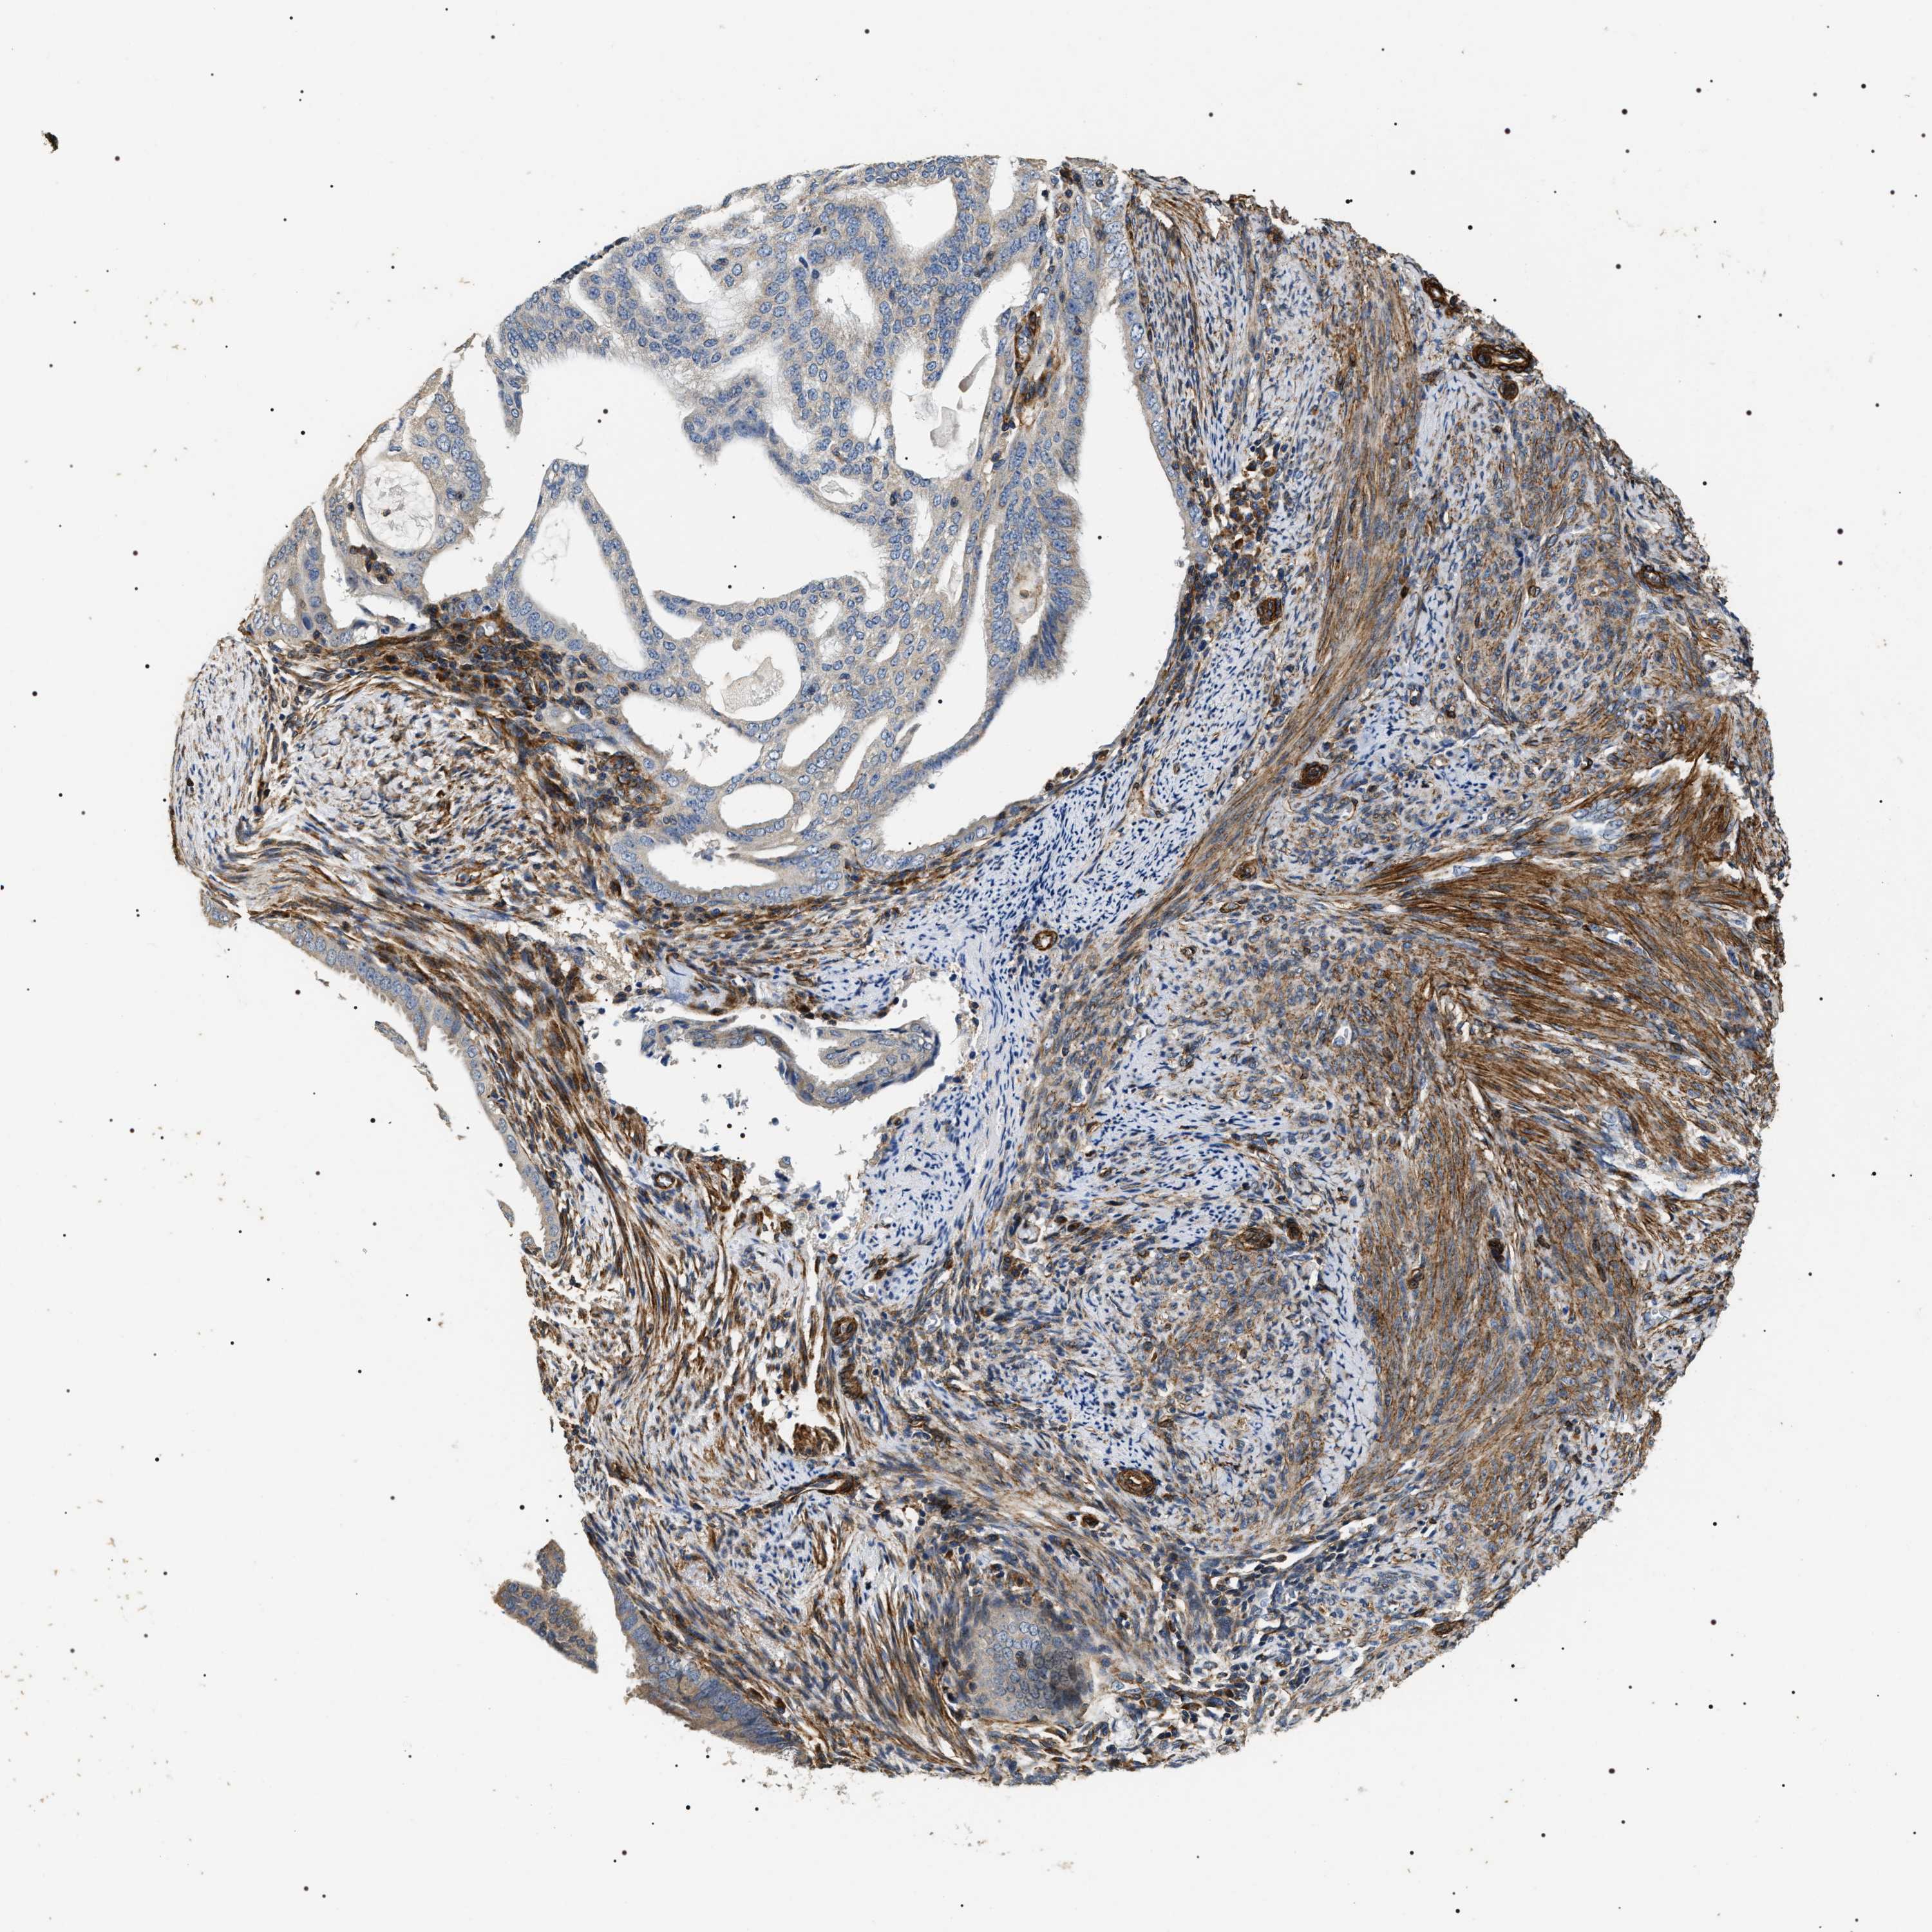

ENDOMETRIAL CANCER - Protein expressioni

A mouse-over function shows sample information and annotation data. Click on an image to view it in a full screen mode. Samples can be filtered based on level of antibody staining by selecting one or several of the following categories: high, medium, low and not detected. The assay and annotation is described here.

Note that samples used for immunohistochemistry by the Human Protein Atlas do not correspond to samples in the TCGA dataset.

Antibody stainingi

Antibody staining in the annotated cell types in the current human tissue is reported as not detected, low, medium, or high, based on conventional immunohistochemistry profiling in selected tissues. This score is based on the combination of the staining intensity and fraction of stained cells.

Each image is clickable and will lead to virtual microscopy that enables deeper exploration of all samples and also displays staining intensity scores, fraction scores and subcellular localization as well as patient and tissue information for each sample.

Antibody HPA020386

Staining

High

Medium

Low

Not detected

Intensity

Strong

Moderate

Weak

Negative

Quantity

>75%

75%-25%

<25%

None

Location

Nuclear

Cytoplasmic/membranous

Cytoplasmic/membranous,nuclear

Adenocarcinoma, NOS

Adenoma, NOS